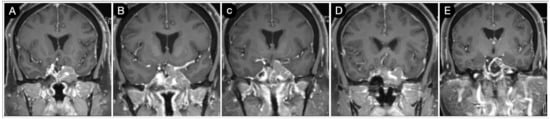

3.2.2. Case #3: Paramedian Pattern of Growth with Parenchymal Invasion